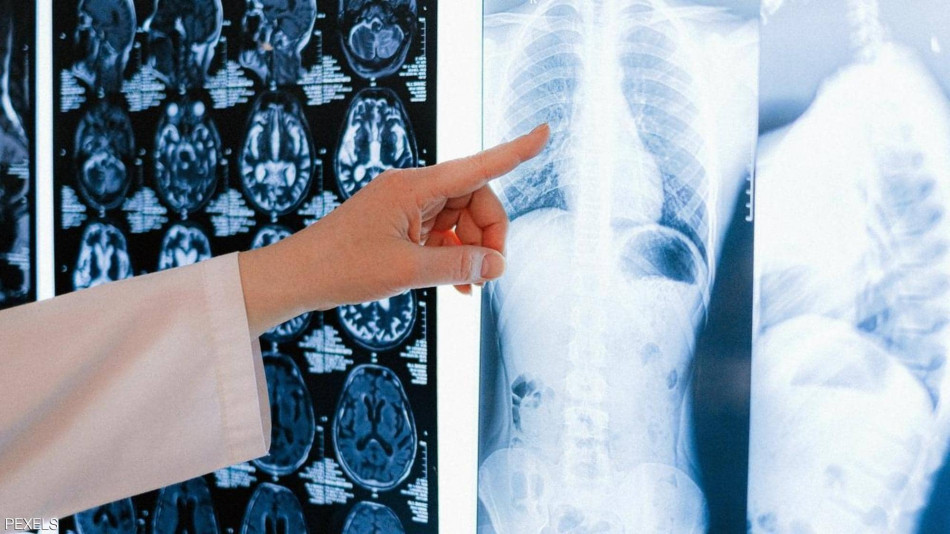

يعاني مجموعة من الأشخاص ممن أصيبوا بفيروس كورونا من التهاب في الرئتين بنسب مئوية مختلفة، قد تؤثر على وظيفة الرئتين عند وصول المصاب إلى حالة حرجة، فماذا يحدث للرئة عندما يصاب الشخص بمرض كوفيد-19؟

كشفت دراسة حديثة أجريت بالمعهد الكوري المتقدم للعلوم والتكنولوجيا بكوريا الجنوبية، سبب تلف الرئة الناجم عن الإصابة بفيروس كورونا، إذ اكتشف العلماء “نوعا فرعيا معينا من البلاعم التي نشأت من خلايا الدم الأحادية”، له دور أساسي في الاستجابة الشديدة للالتهابات في الرئتين المصابتين بكوفيد-19″.

وكشف العلماء أنه في مراحل الإصابة المبكرة من كوفيد-19، عندما تصاب أنسجة الرئة بفيروس كورونا، يتم تنشيط جهاز المناعة بشكل فوري، وتسمى هذه الاستجابة المبكرة والسريعة بـ”المناعة الفطرية” التي توفرها الخلايا المناعية المقيمة في الرئتين.

وحسب معطيات منظمة الصحة العالمية يعاني كل مصاب من بين 6، من أعراض خطيرة تصل إلى الالتهاب الرئوي، وتصنف هذه الإصابات ضمن الحالات الحرجة.